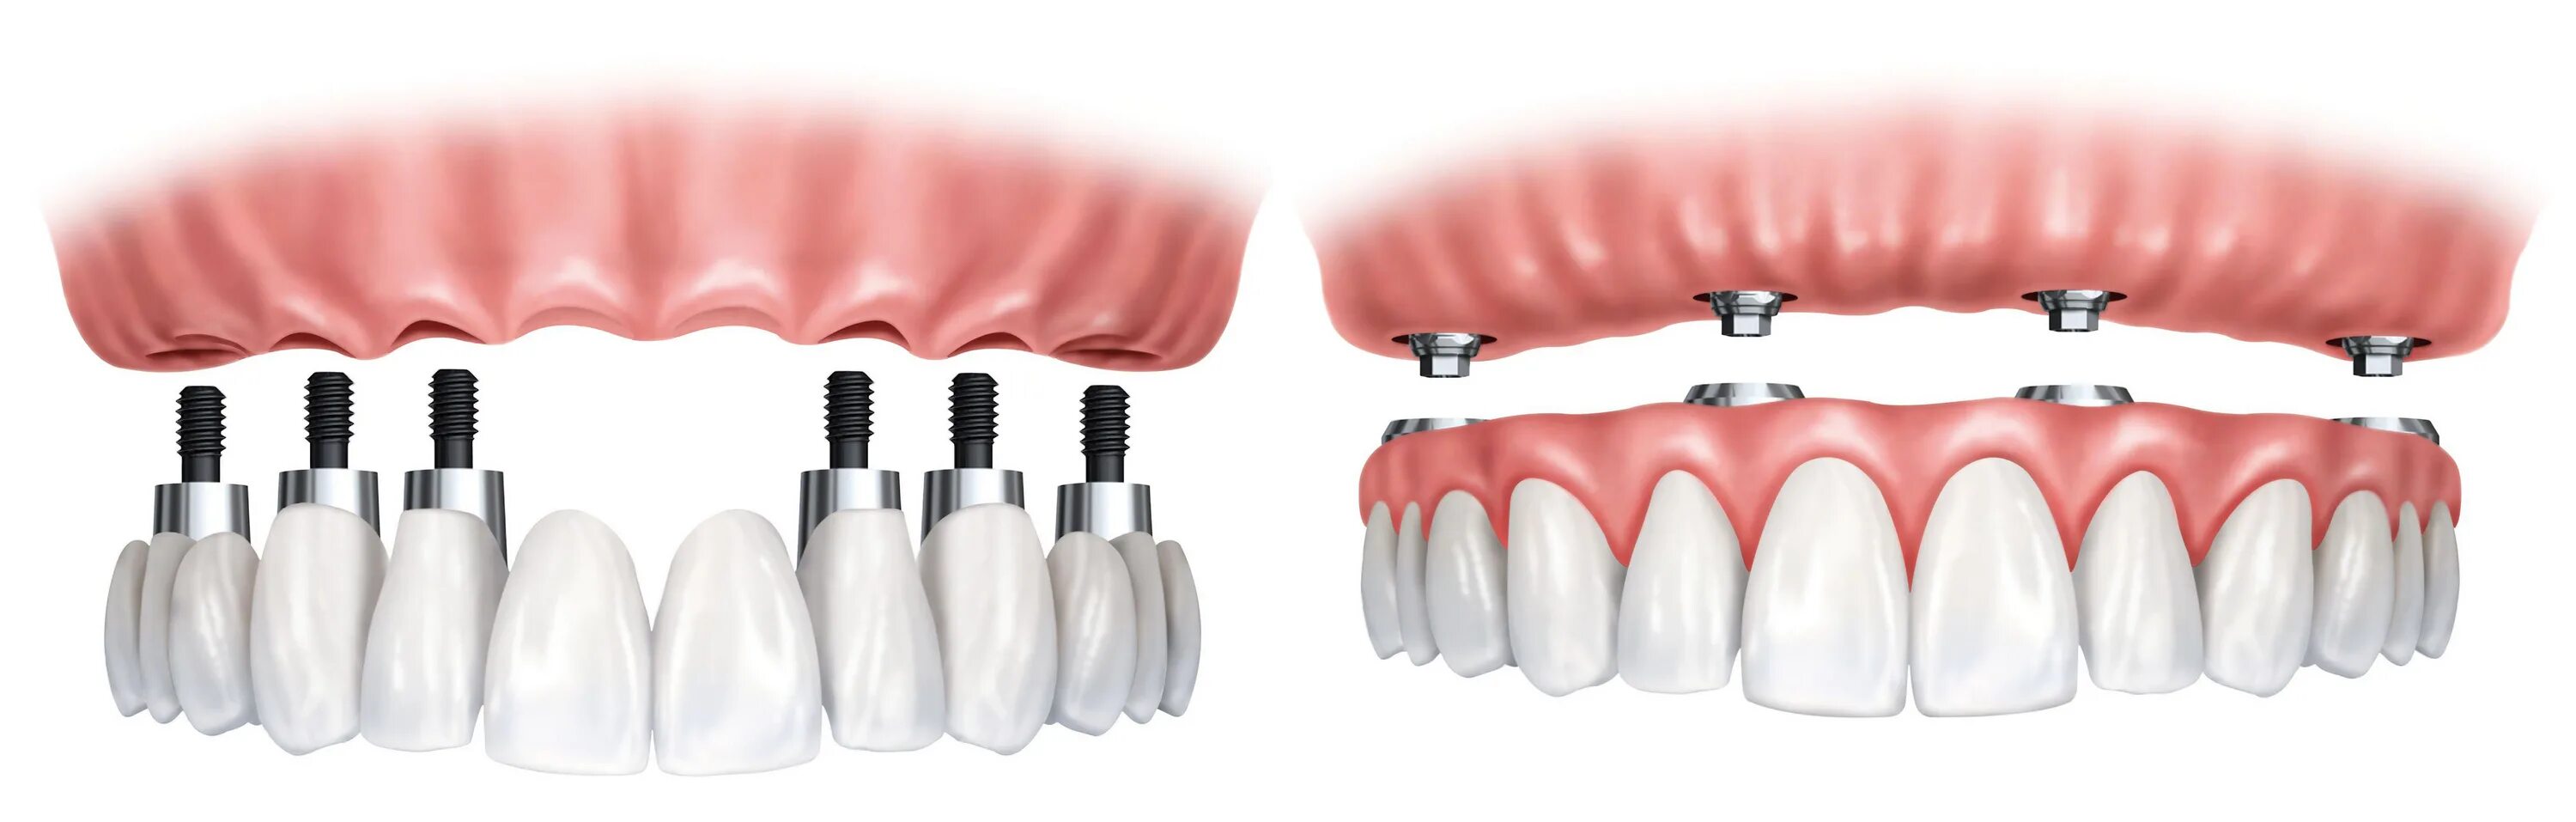

Ол он 4